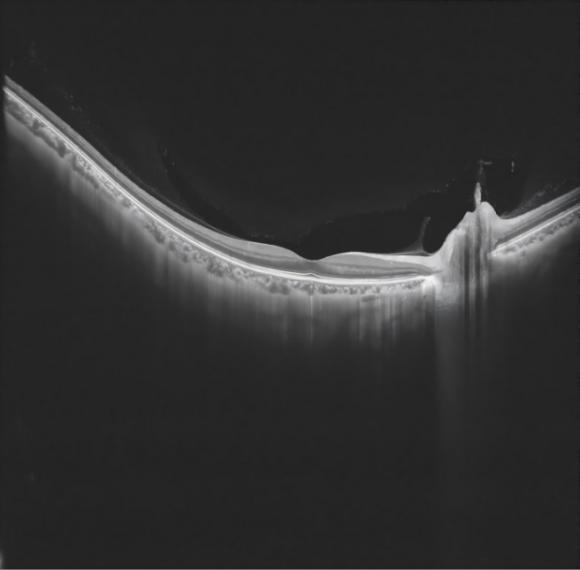

Adams-DAQ1G是一款8bit双通道高速波形数字化仪卡,采用简化信号幅度控制与 Trigger 电路设计,实现高速、高保真、同步、低噪声性能,性能表现优于主流 1G 采集卡,完美适配 OCT、激光雷达、高频超声等对速度、精度、时序要求严苛的场景,支持 OEM 嵌入式集成。

Adams_DAQ1G 目前已经在Intalight 赛炜(全球高端光学眼科器械平台型企业)研发的光学相干断层扫描(OCT) Model:MT700NO:MC0023中采用。

Adams-DAQ1G 采集卡在应用中图像质量展示